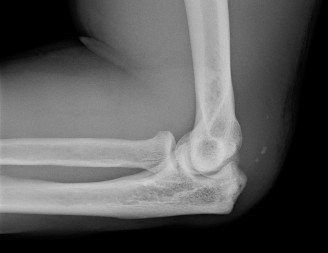

Standard radiographic evaluation of the thrower's elbow must include true anteroposterior (AP), lateral, oblique, and axial (cubital tunnel) views. In this patient, the AP view may appear relatively unremarkable, though subtle hypertrophy of the medial epicondyle or radiocapitellar sclerosis may be noted. The true lateral radiograph is highly informative, often demonstrating the presence of a posterior olecranon osteophyte.

However, the most critical view for diagnosing VEO is the internal rotation oblique view, or a specialized axial view of the olecranon fossa. In our patient's radiographs, we observe a distinct, hypertrophic osteophyte on the posteromedial aspect of the olecranon process. There are also faint radiopacities within the posterior compartment, highly suggestive of intra-articular loose bodies resulting from the fragmentation of these osteophytes.